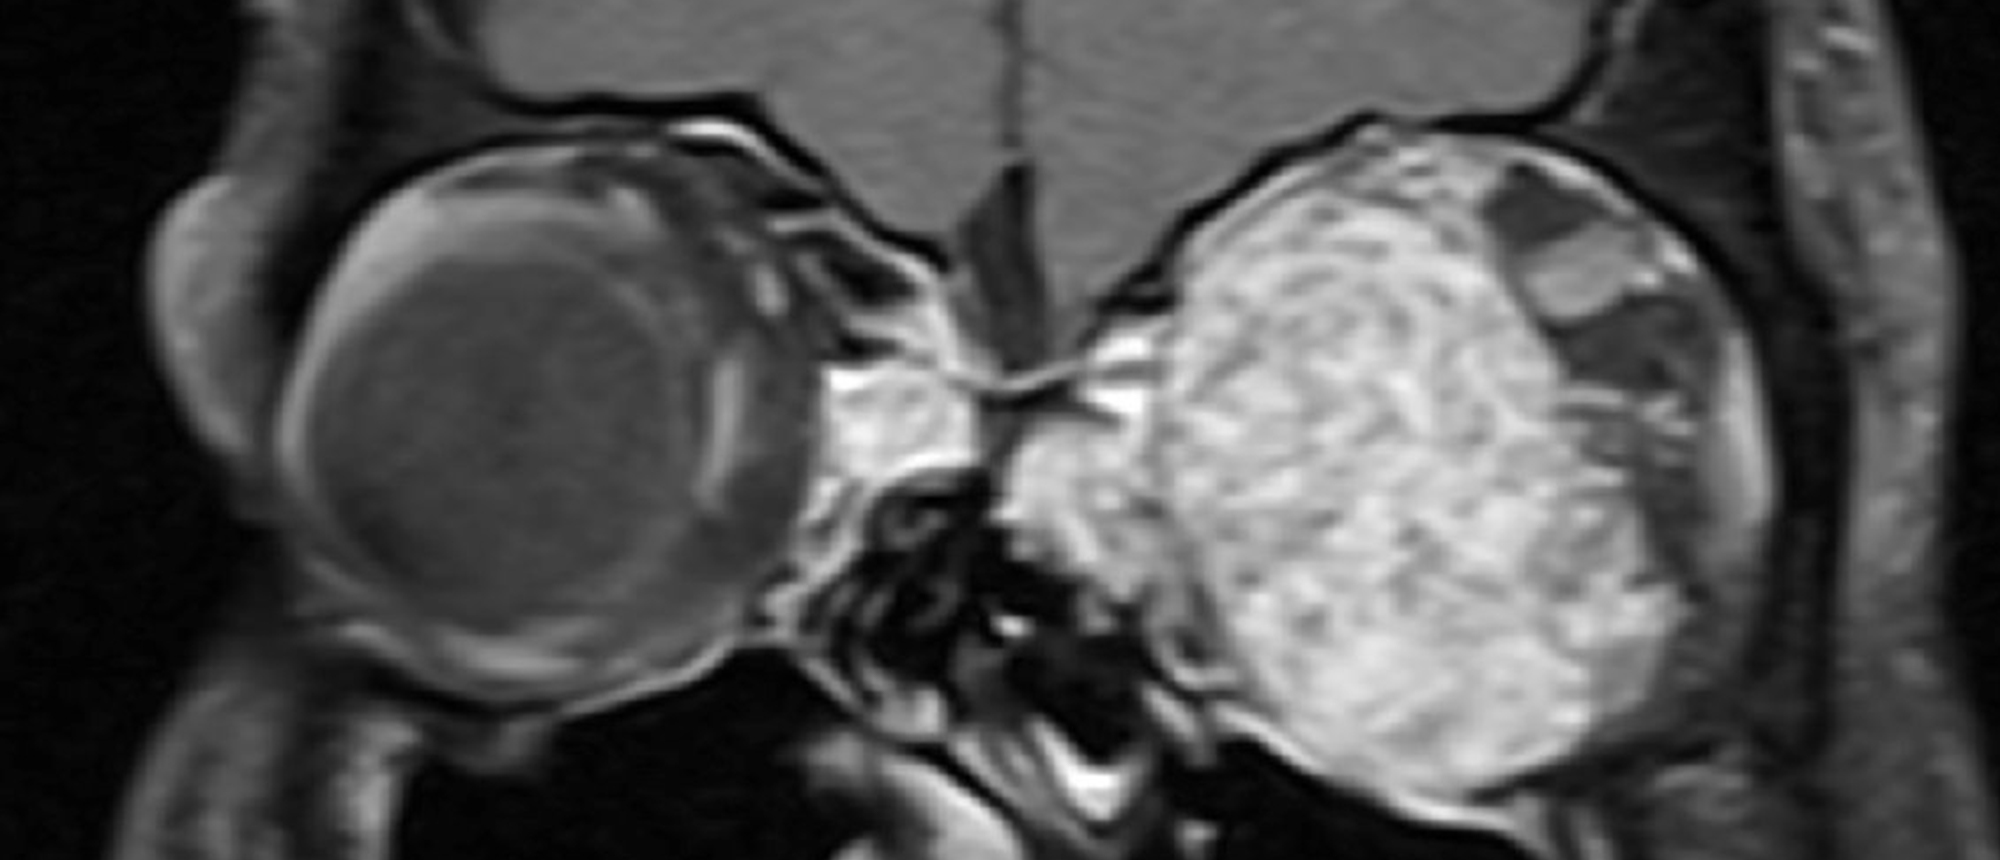

Orbital Sarcoidosis A patient presented with three months of left eye swelling and pain. He was found to have periorbital firmness and fullness, proptosis, and conjunctival chemosis. He underwent computed tomography imaging of the orbits with contrast, which demonstrated an ill-defined, irregular a…